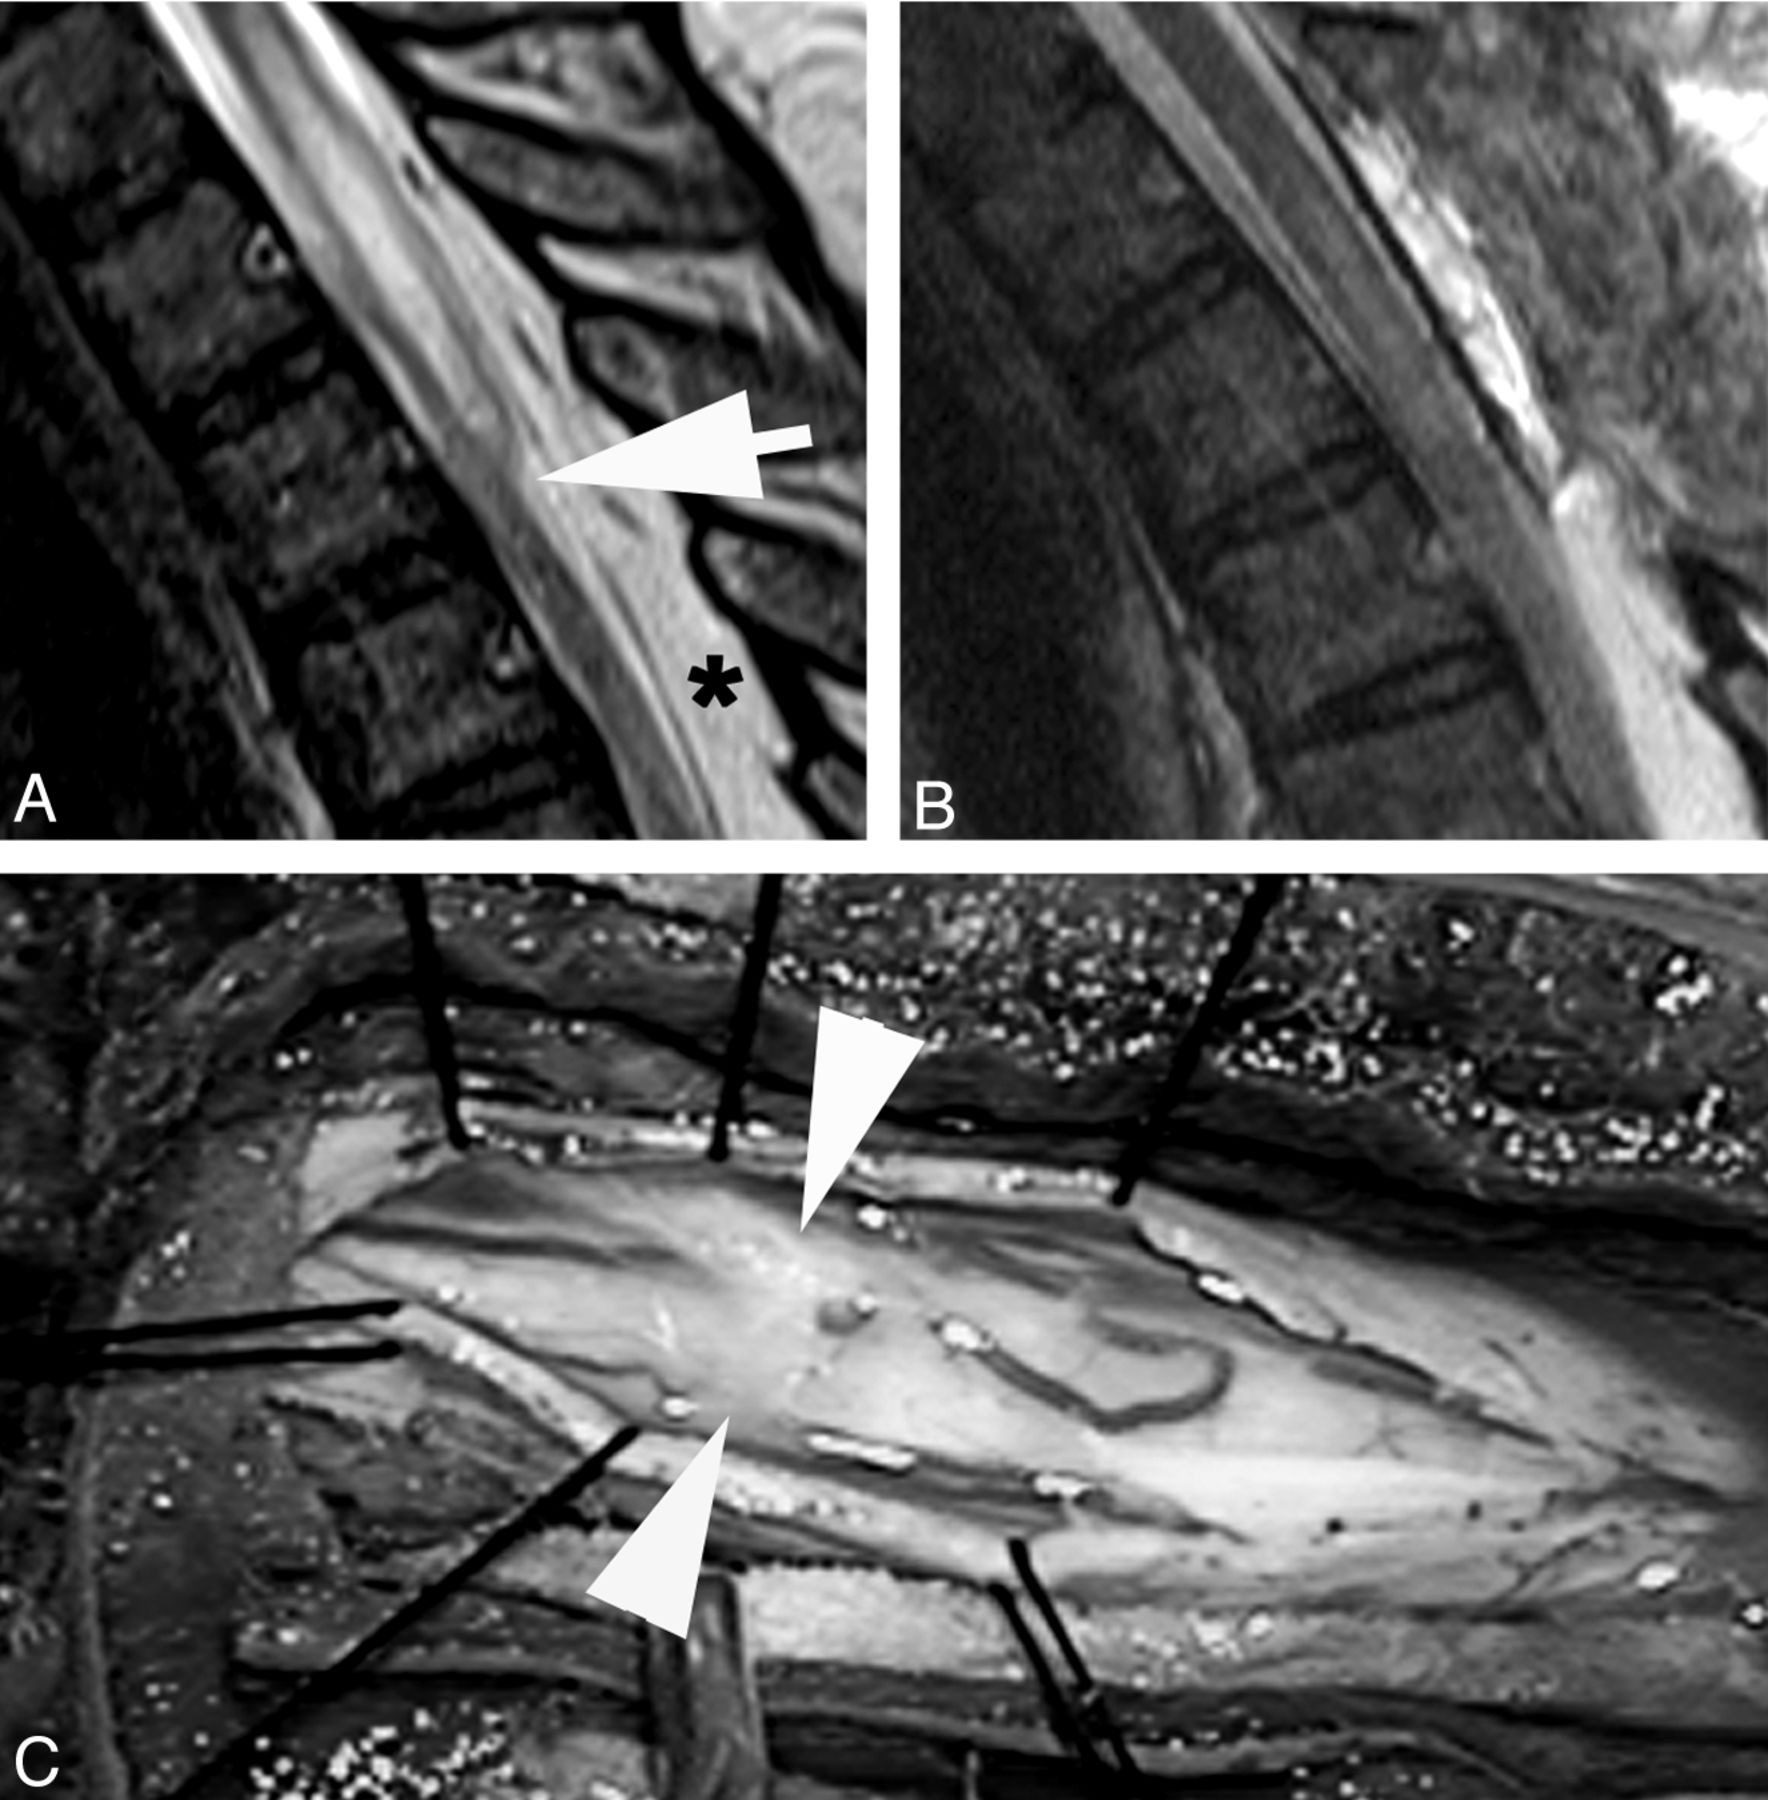

A, T2WI MR image demonstrates a focal dorsal indentation in the upper thoracic spinal cord (arrow). Note prominent epidural fat (asterisk). B, T2WI MR image status post–posterior laminectomy and lysis of a dorsal arachnoid web demonstrates resolution of the dorsal indentation, improved cord signal, and resolution of the syringomyelia. C, Intraoperative image demonstrates the dorsal arachnoid web (between the white arrowheads) before lysis of the web.

A 51-year-old woman presented with an 8-year history of low back pain and 1 year of intermittent midback pain and bilateral shoulder pain. She did not have radicular pain or numbness, and there was no history of trauma or spinal surgery. MR imaging demonstrated a focal indentation along the dorsal surface of the spinal cord at the T4 vertebral body level (Fig 3). Increased T2WI signal with cord expansion and syringomyelia extended from T1 to T3. Cord signal inferior to the focal deviation was normal. A significant amount of posterior epidural fat was not directly compressing the cord. It was hypothesized that the appearance of the spinal cord deviation was secondary to an arachnoid web. The patient underwent T2-T4 laminectomies for intradural exploration, which revealed kinking of the spinal cord caused by a transverse dorsal arachnoid web at the level of the narrowing. The web was carefully sectioned with visually apparent relief of the kinking. Follow-up MR imaging revealed resolution of the focal cord indentation, decreased T2WI signal abnormality, and resolution of the syringomyelia. The patient reported an improvement in her upper back and shoulder pain but continued to have chronic low back pain.

A, Sagittal T2WI MR image demonstrates a focal dorsal indentation (arrow) in the thoracic spinal cord. B, Intraoperative image after opening of the dura demonstrates an intradural white arachnoid band (between arrowheads) passing transversely across and compressing the dorsal surface of the spinal cord. C, Intraoperative image of the cord after the band of arachnoid tissue has been cut. The position is marked by arrowheads.

A 56-year-old man with a history of multiple sclerosis was evaluated for a 2-year history of episodic bilateral leg paralysis and falls. Symptomatic episodes occurred without warning, lasted approximately 30 minutes, and were relieved with recumbency. The episodes increased in frequency for 6 months before presentation, at which time these episodes were occurring almost daily. MR imaging of the thoracic spine demonstrated a dorsal indentation of the spinal cord with anterior displacement at the T7 level, without abnormal cord signal or syringomyelia. Subsequently, laminectomies were performed from T5 to T9. When the dura was opened, a dense band of arachnoid tissue was seen extending transversely across the posterior aspect of the spinal cord at the T7 level (Fig 5). This resulted in an obvious deformation of the spinal cord with flattening and compression. The anterior dura was explored, and there was no evidence of a ventral dural defect or anterior cord herniation. Surgical lysis of the arachnoid band was performed, and over several minutes, the cord flattening and deformity visibly improved. The patient's leg strength immediately improved bilaterally with more pronounced improvement on the right. He continued to have intermittent slight spasticity in both lower extremities. His coordination slowed when he was fatigued. These symptoms may have been related to his underlying multiple sclerosis. He remained wheelchair-bound, mainly secondary to his lack of coordination. No follow-up imaging was available for this patient.